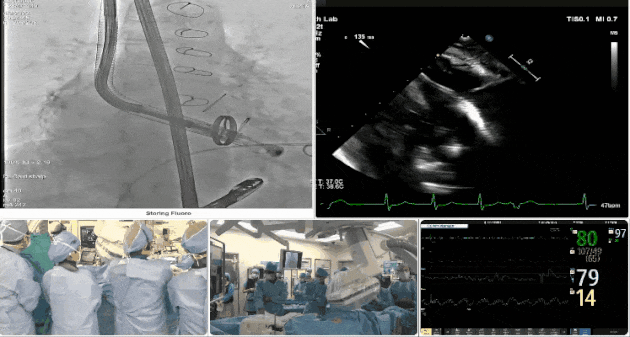

術(shù)中DSA顯示起搏器導(dǎo)線的干擾,右心室造影確定瓣環(huán)位置,操作空間小

術(shù)中TEE成像困難,偽影干擾

術(shù)后DSA、超聲顯示人工瓣膜穩(wěn)定性良好,瓣葉啟閉正常,無瓣周漏